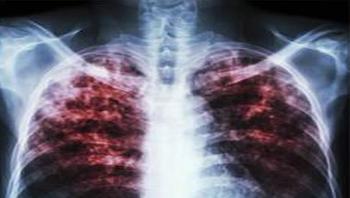

Although tuberculosis (TB) is commonly thought of as being a disease that mainly affects nineteenth century poets and Victor Hugo characters, it is still the second-most common cause of mortality from an infectious disease in the world, killing nearly three people every minute. Every March 24, on World TB Day, the global health community recognizes the work of Robert Koch, who announced on that date in 1882 his discovery of Mycobacterium tuberculosis, the bacteria that causes TB.